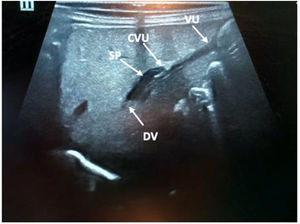

Usando el hígado como una ventana acústica, la anatomía relevante puede visualizarse con la sonda (sectorial o lineal) aproximadamente en la línea media, debajo del xifoides y orientada sagitalmente hacia la cabeza, localizando el territorio de la vena umbilical con la porta (fig. 1).